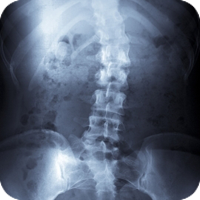

Like other health-care providers, we follow a standard routine to gain information about the patient. We consult, review the case history, conduct a physical examination, and we may request laboratory analyses and/or x-rays. Unlike other health-care providers, however, chiropractic physicians also conduct a careful analysis of the patient's structure and pay particular attention to the spine. We also ask you about your life- Do you eat well? Exercise at all? How do you deal with stress? Do you have children? What do you do for work? And so on.

Chiropractors have a term for misalignments: subluxations. A vertebral subluxation is a misalignment of the bones that protect the spinal cord. It's a leak in the roof. Or a kink in the wiring of your nervous system.  The severity of the subluxation can vary, and there are a number of potential contributing factors that can be physical, emotional, mental, or chemical. The subluxation can be caused by any number of incidents, from birth trauma to an auto accident to simple repetition or over-use.